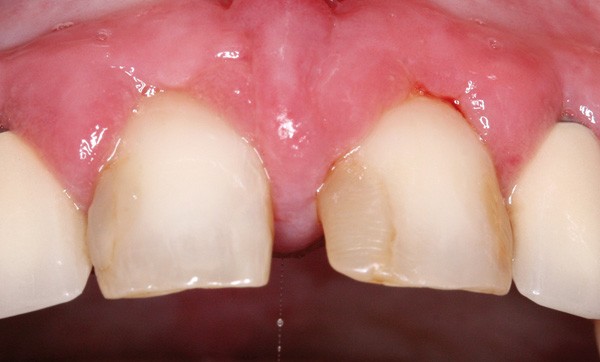

L’examen clinique endobuccal montre un accroissement gingival situé au niveau de la gencive marginale et attachée, généralisé aux arcades maxillaire et mandibulaire, tant sur le versant vestibulaire que lingual. Le reste des muqueuses est strictement normal. La face dorsale de la langue est normale (fig. 2a et b).{{FIG2}}